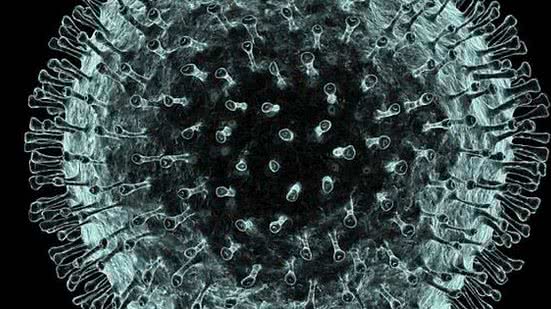

A OMS (Organização Mundial da Saúde) anunciou hoje que criou um nome oficial para a doença causada pelo novo coronavírus em uma coletiva de imprensa realizada em Genebra. Ela será chamada de COVID-19.

A OMS (Organização Mundial da Saúde) anunciou hoje que criou um nome oficial para a doença causada pelo novo coronavírus em uma coletiva de imprensa realizada em Genebra. Ela será chamada de COVID-19.